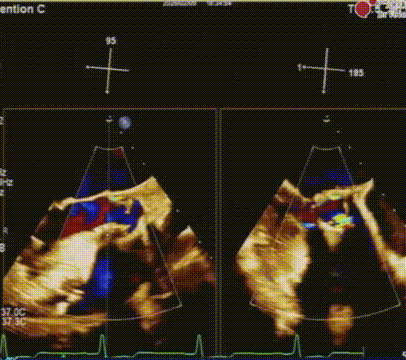

心脏超声示:

重度主动脉瓣狭窄合并中度反流,EF: 46%,AV MPG: 57 mmHg,AV 4.9 m/s,LVIDd: 54 mm。

瓣膜释放后食道超声评估

术后食道超声评估